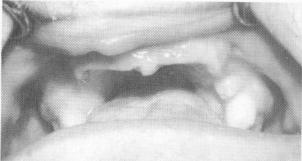

Fig. 15-2. Clinical view of the maxilla.

1 Clinical view of the maxilla, for implant intervention